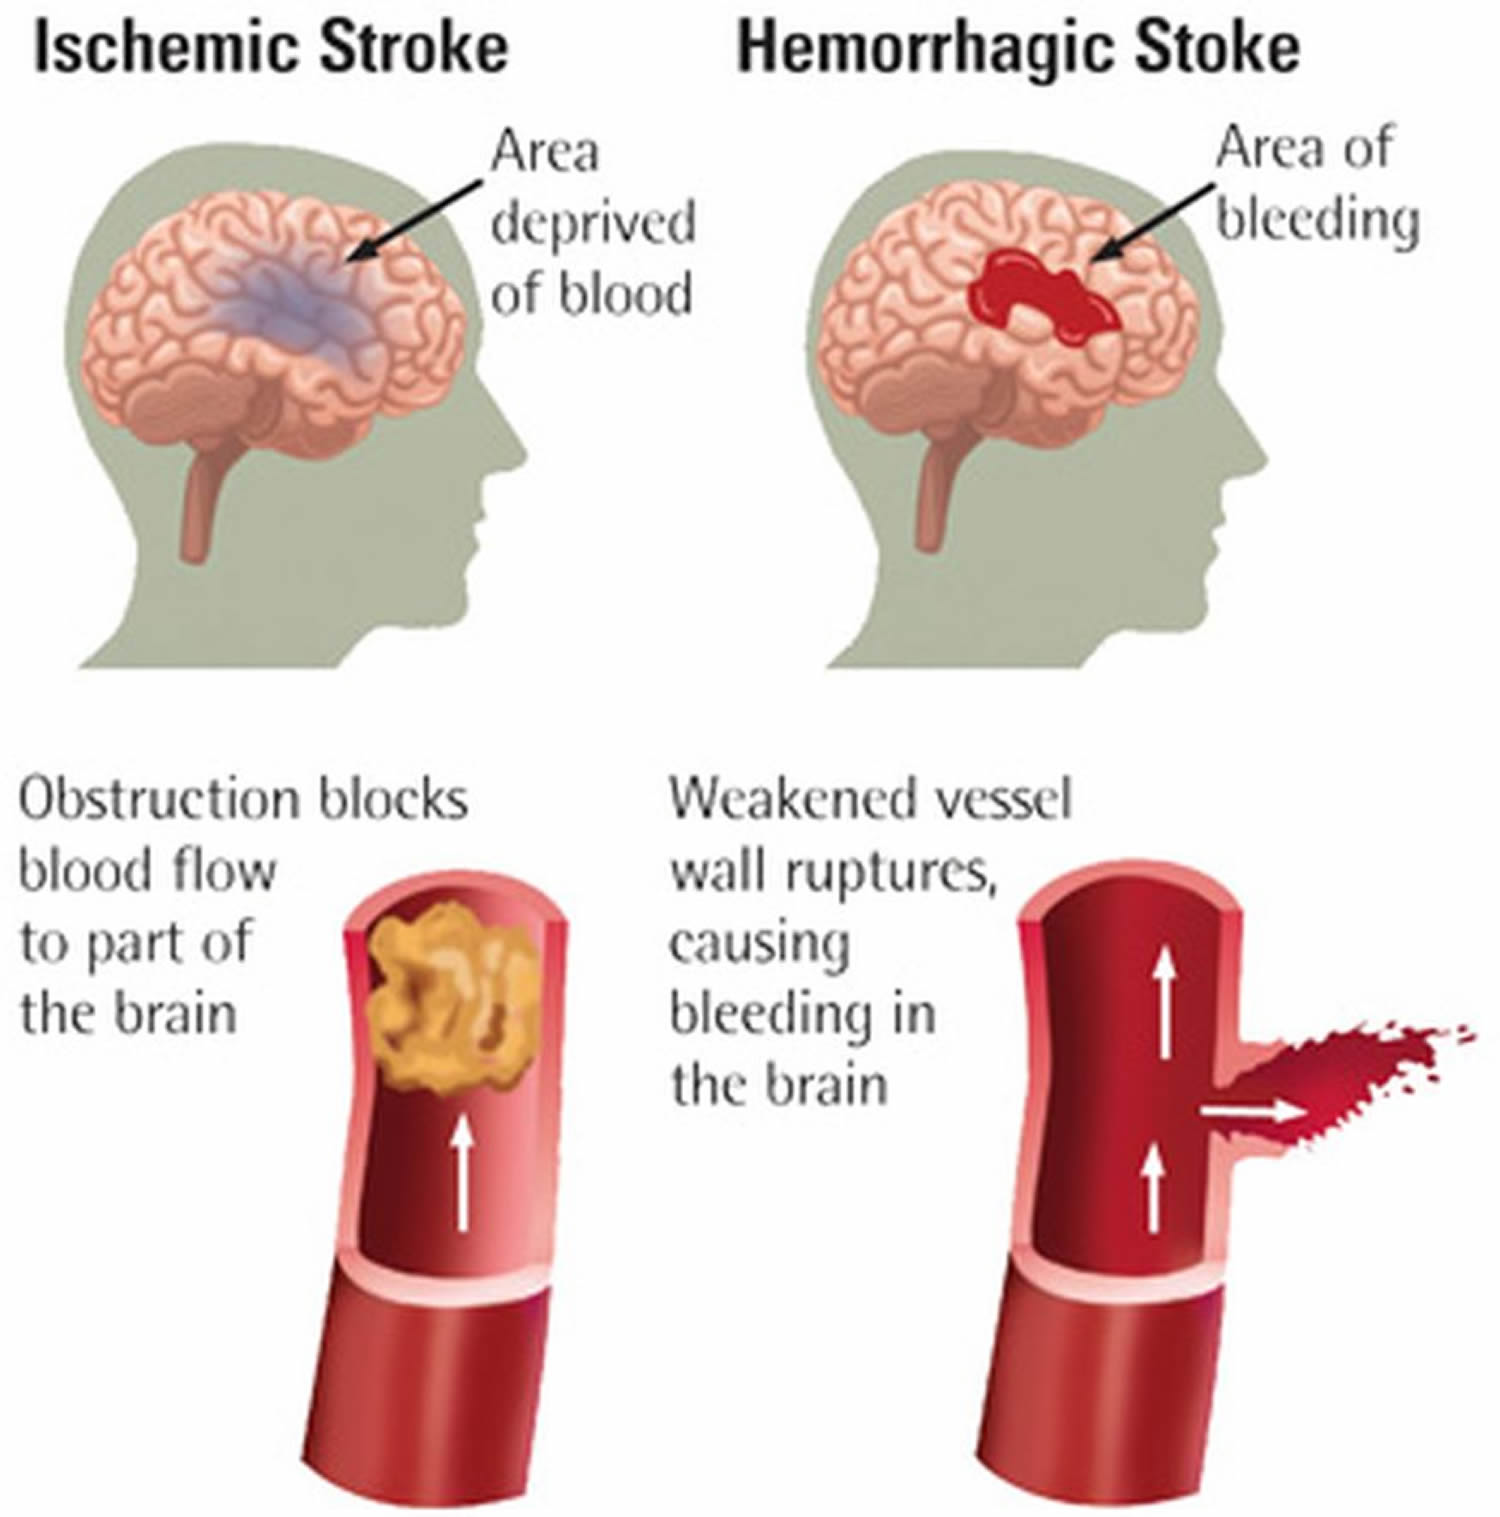

Ischemic Stroke Causes Signs Symptoms Ischemic Stroke Treatment

Ischemic Stroke Causes Signs Symptoms Ischemic Stroke Treatment